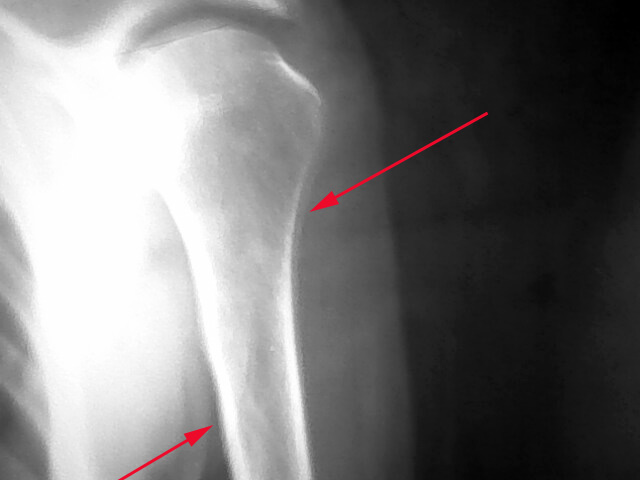

男,76。上臂软组织包块

片子太虚了,箭头所指考虑模糊伪影所致

不太像你说的软组织包块,我倒是人为可能是拍照时病人动了以后所产生的,而且如果说是骨膜反应也不是太确切。总之我认为不像软组织包块!(个人意见)

骨膜反应,须在复查观察

不是骨膜反应。整个片子感觉太模糊。照相时病人动了吧。重新照一下不就行了

整个片子感觉太模糊,重照吧。假如骨膜弥漫性增厚,要考虑肺部病变。

骨膜伴随影。